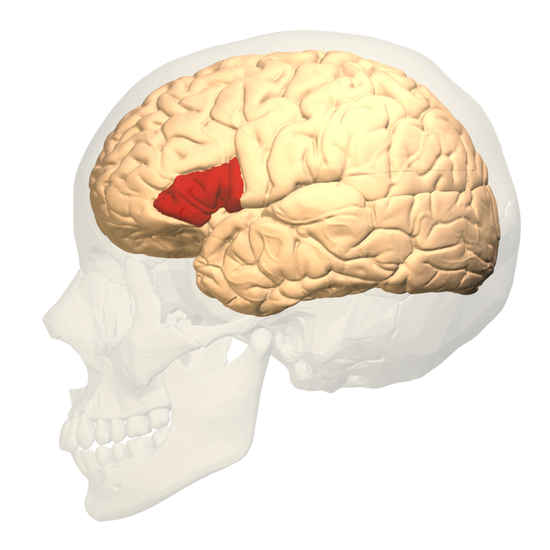

人类的大脑分成左右两个半球,每个半球又有四个叶:额叶在前面,颞叶在外侧,顶叶在上方,枕叶在后部。

其中,语言功能主要靠颞叶和额叶来实现。颞叶承载着一个重要区域,名叫韦尼克区(Wernicke‘s Area),位在颞叶与顶叶交界的地带,可以帮助我们理解语言,不论是听到的语音还是看到的文字;额叶也有一个重要区域,名叫布洛卡区(Broca‘s Area),它能为我们选取合适的词汇,表达出自己的想法。

左脑和右脑都有颞叶和额叶,但两个脑半球的功能却有所不同。对大多数人(85~90%)来说,左脑会成为处理语言的主要担当,也成为优势半球,而右脑语言区的功能则会受到抑制。

假如你还记得,本文主人公EG丢失的正是左脑的颞叶。可是她的语言能力并无明显缺陷,甚至还优于常人(除了拼写容易出错)。所以,科学家十分珍惜这个找上门来的案例。